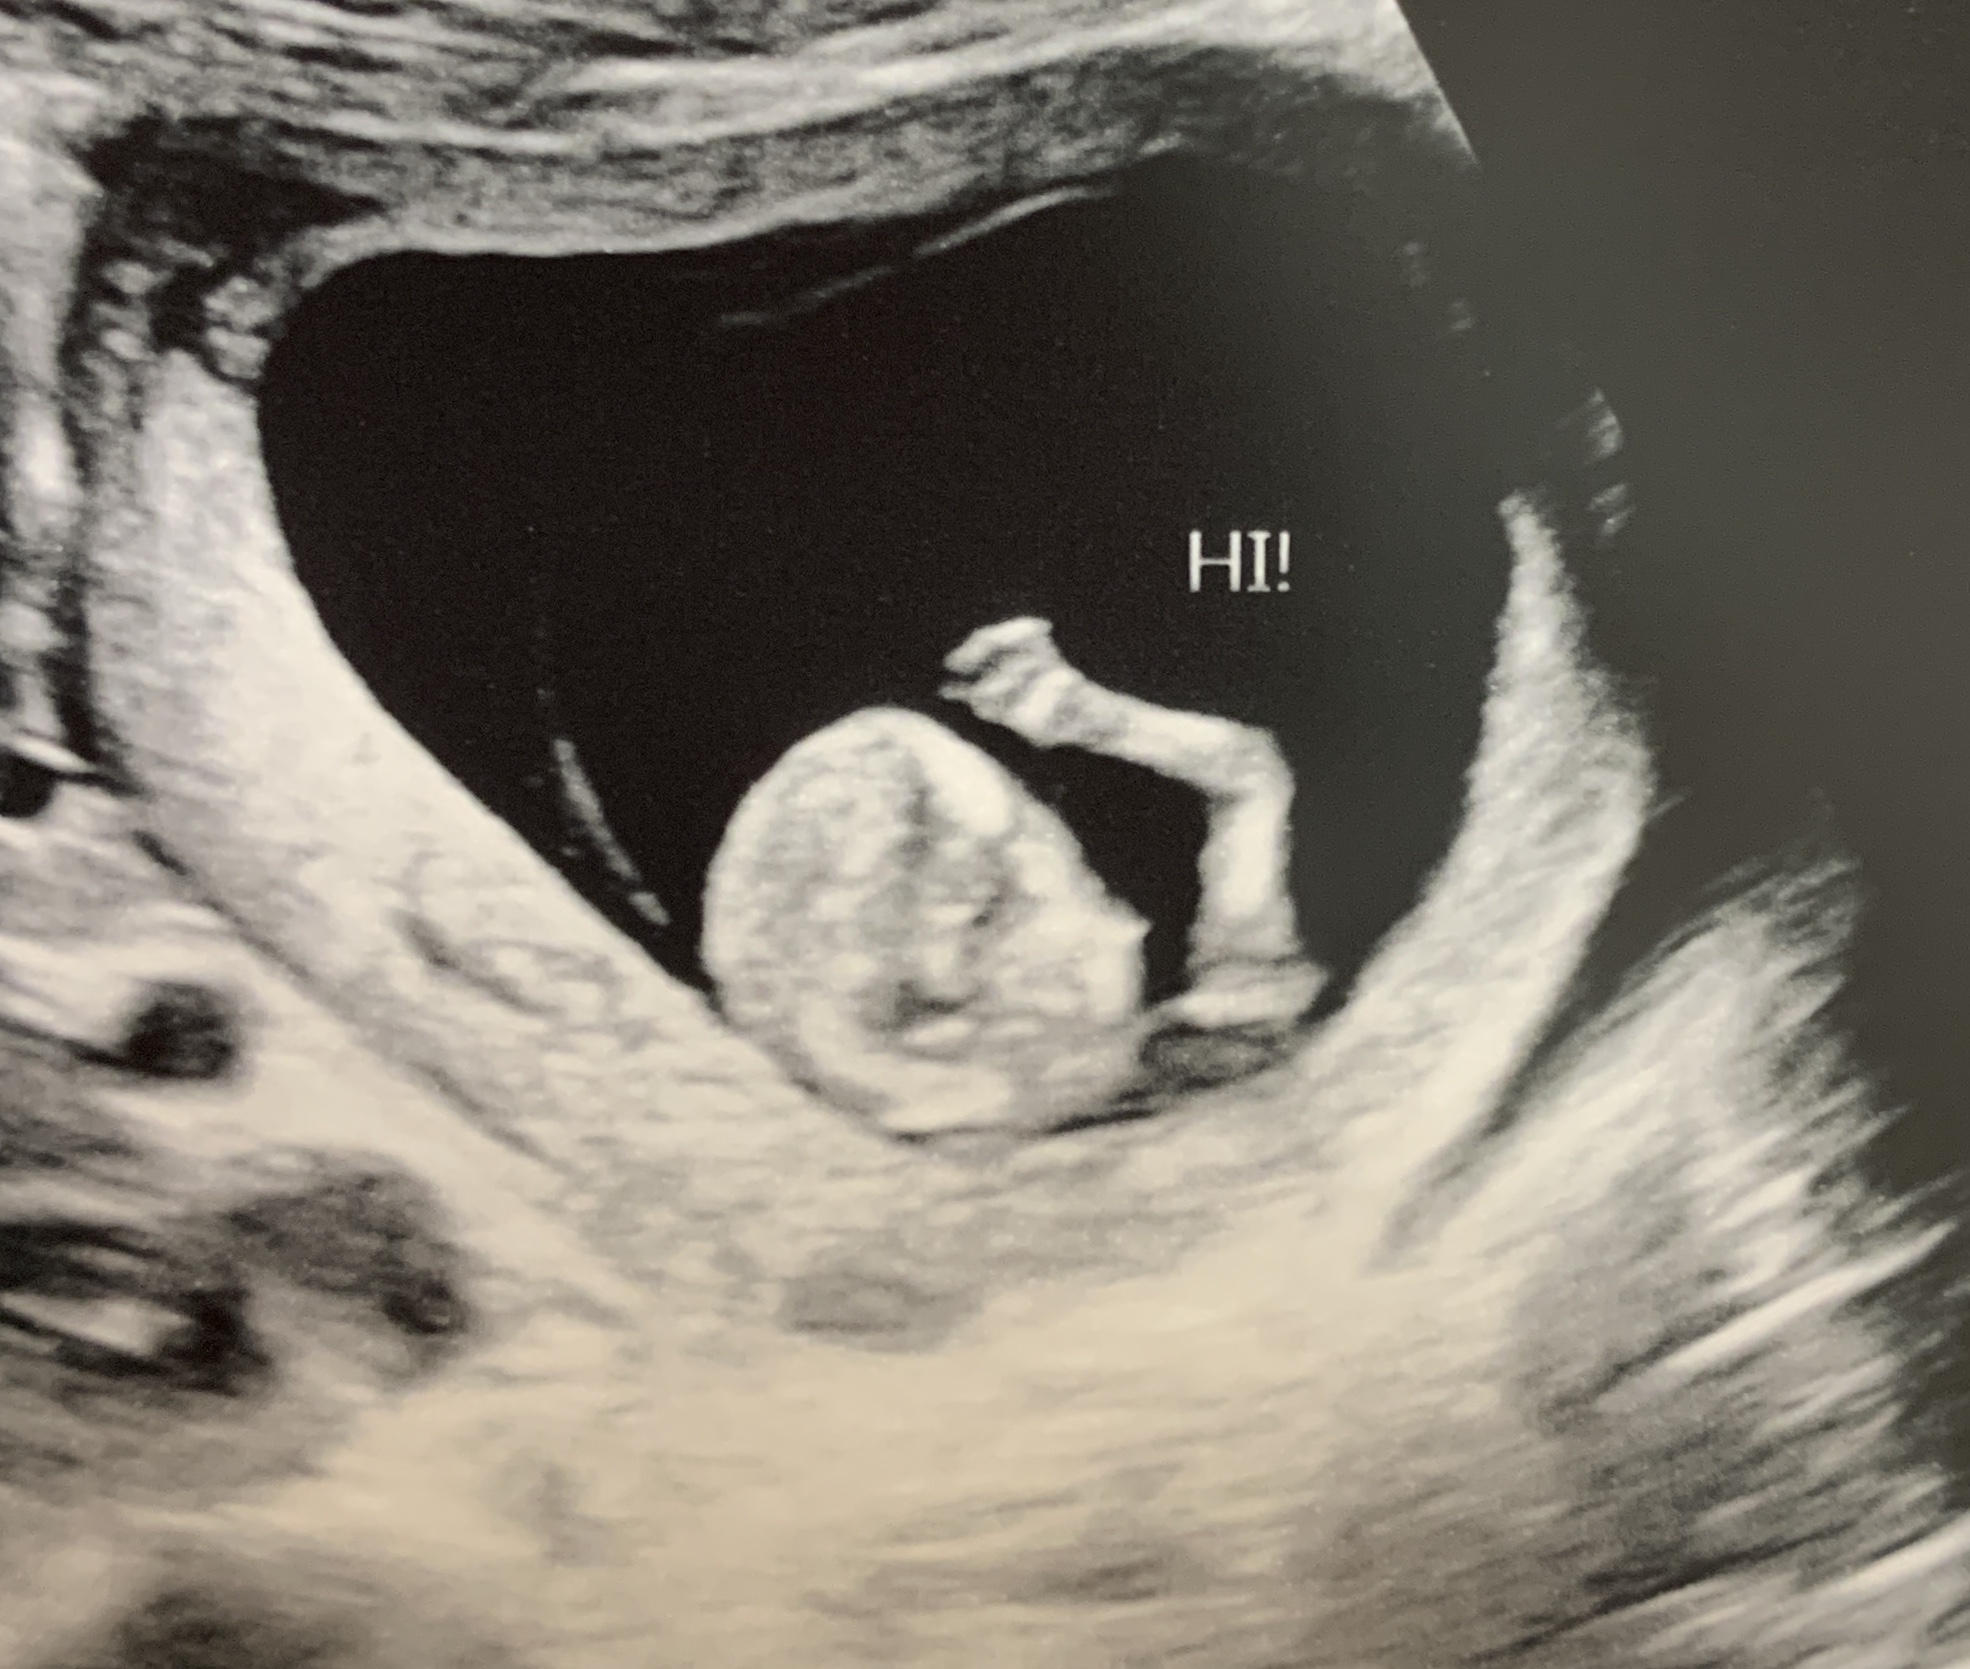

Anyway, I think we were closing in on Maria June at around 3 months pregnant when I had some sudden and serious pains, and my doc asked me to come in for a quick scan for the heartbeat. They couldn’t find the heartbeat with the doppler (which is normal for 11 weeks, but still made me nervous) so they sent me in for an ultrasound…and there was my second daughter, WAVING AT ME. It felt like the most mischievous, attention-seeking move ever…scare me with pains and don’t show up for the heart scan just so we can put you on the camera and see you wave!? It felt like my daughter was already showing her personality, and that personality did not match the image I had of a “Maria June.” Maria June seemed too proper…too by-the-rules to pull a stunt like that. Goldie seemed a little more playful and mischievous. I know I shouldn’t ascribe ANY personality traits to my kid, especially this early, but that little episode just sent me directly down another path as far as her name was concerned and there was no turning back.